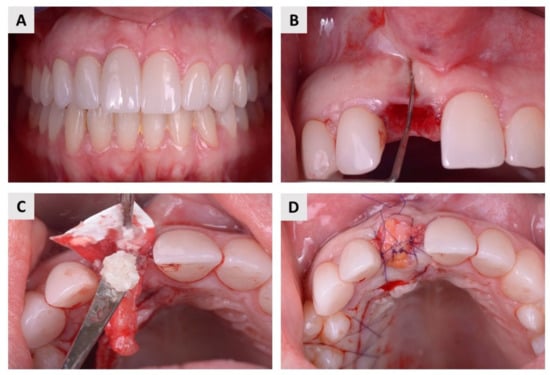

2.1. Clinical Evaluation

4.2. Surgical Procedure and Postoperative Follow-Up